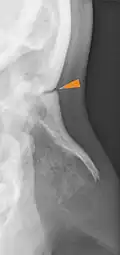

Frontonasal suture

The frontonasal suture (Latin: Sutura frontonasalis) is a cranial suture that is found in the human skull, connecting the frontal bone and the two nasal bones.[1] This suture meets the internasal suture at the nasion. It is crucial in the study of cranial development and forensic analysis.